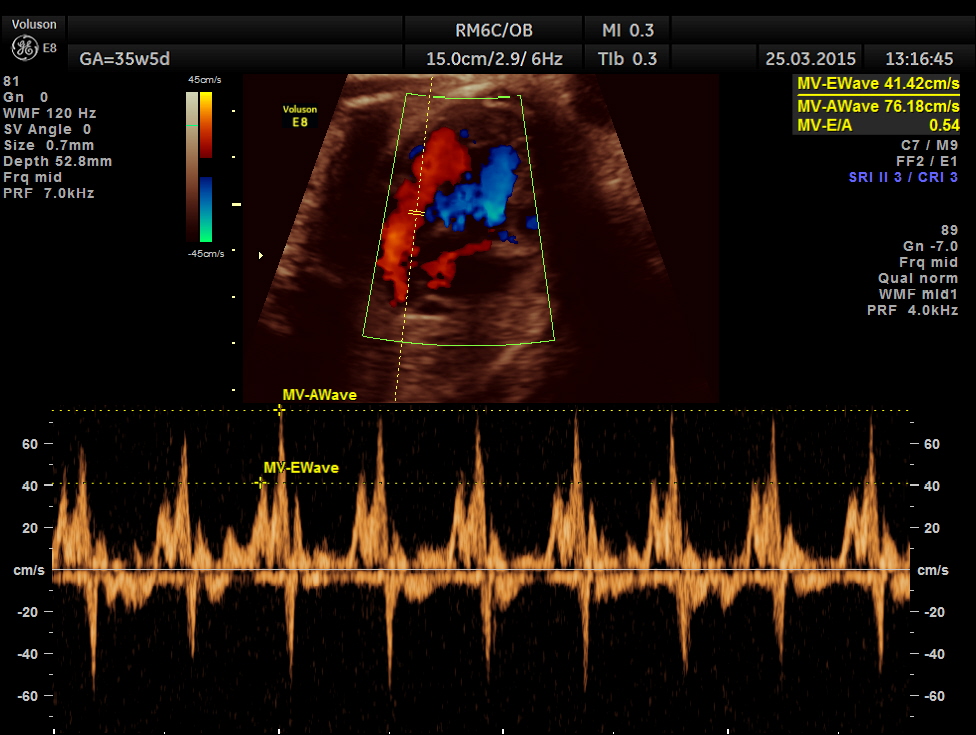

Mitral valve doppler flow.